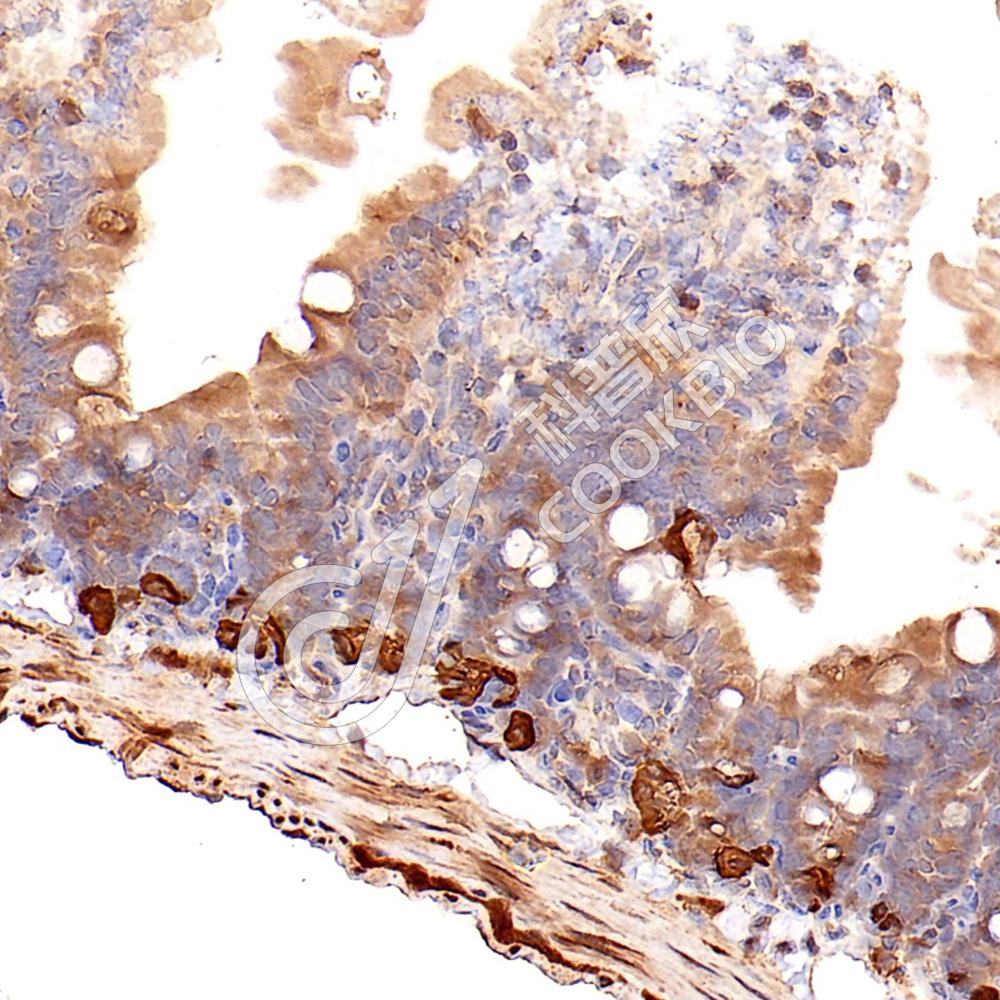

IHC检测SPINK5/LEKTI蛋白(货号 K1335718).

样品: 人子宫颈, 4%多聚甲醛 (货号KSG1101) 固定12-24小时.

抗原修复: 柠檬酸抗原修复液(干粉, pH 6.0) (KSG1201), 98℃, 20分钟.

—抗: 1: 1300稀释, 4℃ 孵育过夜.

二抗: S-vision免疫组化多聚二抗(山羊抗兔),即用型 (货号KB3906), 室温孵育20分钟.

样品: 人扁桃体, 4%多聚甲醛 (货号KSG1101) 固定12-24小时.